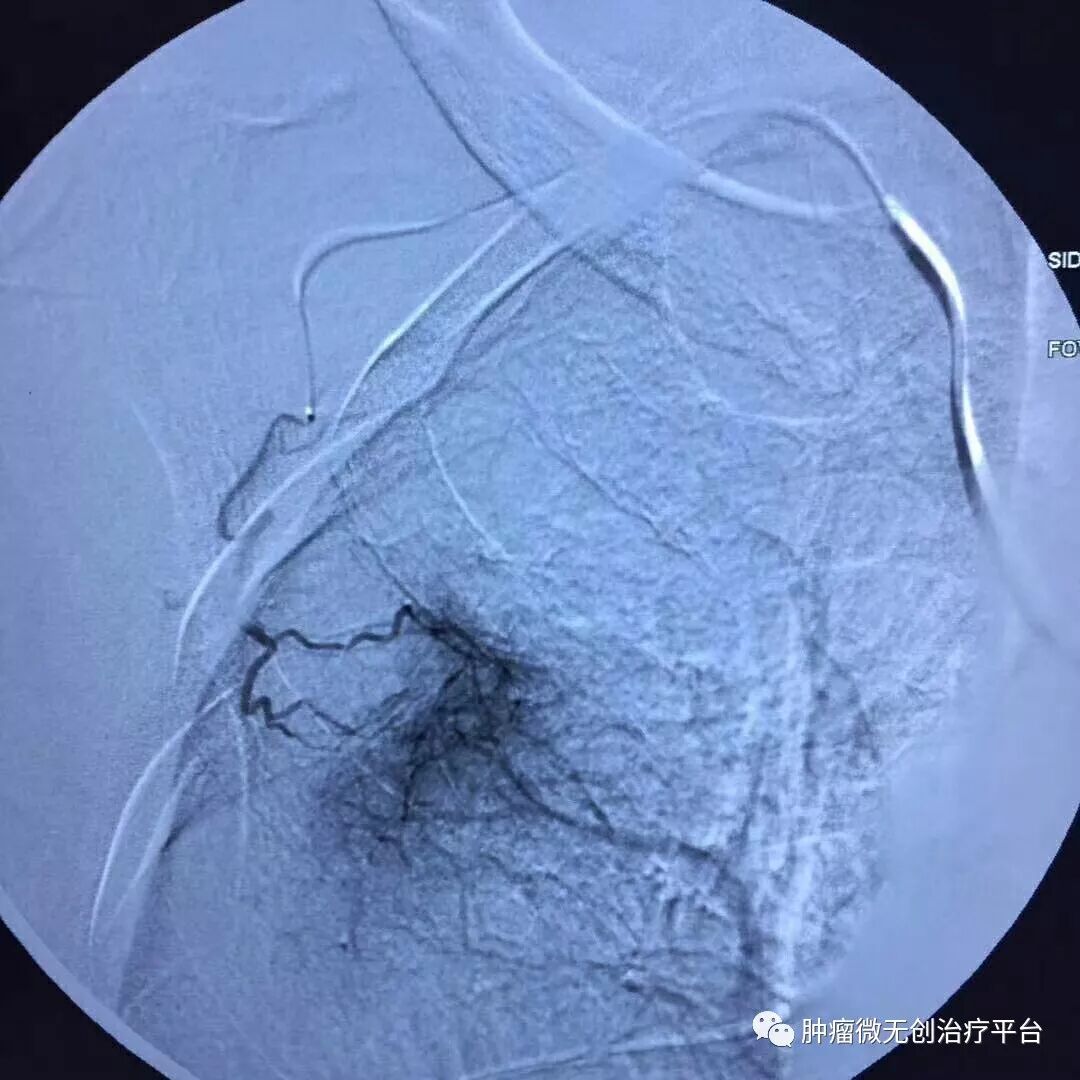

患者情况高龄(79岁)右肺腺癌侵犯胸壁患者肿瘤供血动脉栓塞➕氩氦刀冷冻消融术:图1-2术前PET-CT;图3术前CT;图4-5肿瘤供血动脉栓塞介入;图6-9氩氦刀冷冻消融治疗。